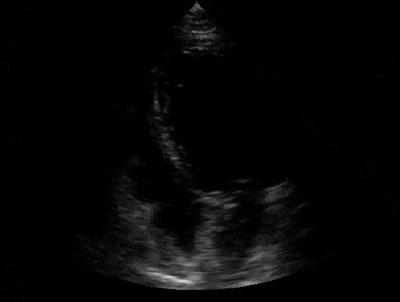

![]() |

| Above: Unenhanced echocardiogram. Below: Echocardiogram enhanced with Definity (Bristol-Myers Squibb Medical Imaging, North Billerica, MA). Image courtesy of Bristol-Myers Squibb Medical Imaging. |